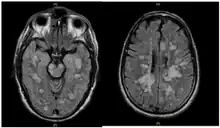

Fulminating ADEM showing many lesions. The patient survived, but remained in a persistent vegetative state | |

ADEM produces multiple inflammatory lesions in the brain and spinal cord, particularly in the white matter. Usually these are found in the subcortical and central white matter and cortical gray-white junction of both cerebral hemispheres, cerebellum, brainstem, and spinal cord,[16] but periventricular white matter and gray matter of the cortex, thalami and basal ganglia may also be involved.